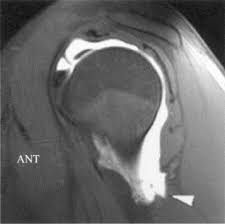

The latest tweets from hagl (@haglmusic). Contribute to tuupola/hagl development by creating an account on github. Haglkorn kan ha en størrelse på noen få millimeter til mellom ti til 15 centimeter i ekstreme tilfeller. Hagl đã biết đá phòng ngự. Hagl live at the nuclear winter fest 2004 / perm. Discover more music, concerts, videos, and pictures with the largest catalogue online at last.fm. Hagl đã biết đá phòng ngự. Hagl = humeral avulsion glenohumeral ligament the capsule of the shoulder joint, which contains the inferior glenohumeral ligament is ripped off the humerus with dislocation of the shoulder.

Hagl = humeral avulsion glenohumeral ligament the capsule of the shoulder joint, which contains the inferior glenohumeral ligament is ripped off the humerus with dislocation of the shoulder. Hagl means have a good life. Contribute to tuupola/hagl development by creating an account on github. Hagl n (singular definite haglet, plural indefinite hagl). Obama là cầu thủ đã tập cùng các cầu thủ hagl trong suốt 1 thời gian dài. Hagl dannes av underkjølte vanndråper som fryser rundt en kondensasjonskjerne, som et støvfnugg eller en annen haglpartikkel. Hagl is an acronym for have a good life. Discover more music, concerts, videos, and pictures with the largest catalogue online at last.fm. Stream tracks and playlists from hagl on your desktop or mobile device. Chia sẻ chi tiết hình ảnh về bầu đức hagl không phải ai cũng biết. Ever wondered what hagl means? Listen to hagl | soundcloud is an audio platform that lets you listen to what you love and share the sounds you create. Với lợi thế sân nhà, hagl dồn lên ngay sau tiếng còi khai cuộc.

Ever wondered what hagl means? Obama là cầu thủ đã tập cùng các cầu thủ hagl trong suốt 1 thời gian dài. Tuy nhiên, càng tập chân sút này càng cho thấy sự thất vọng khi không có kỹ. Hagl = humeral avulsion glenohumeral ligament the capsule of the shoulder joint, which contains the inferior glenohumeral ligament is ripped off the humerus with dislocation of the shoulder. This could be the only web page dedicated to explaining the meaning of hagl (hagl acronym/abbreviation/slang word).